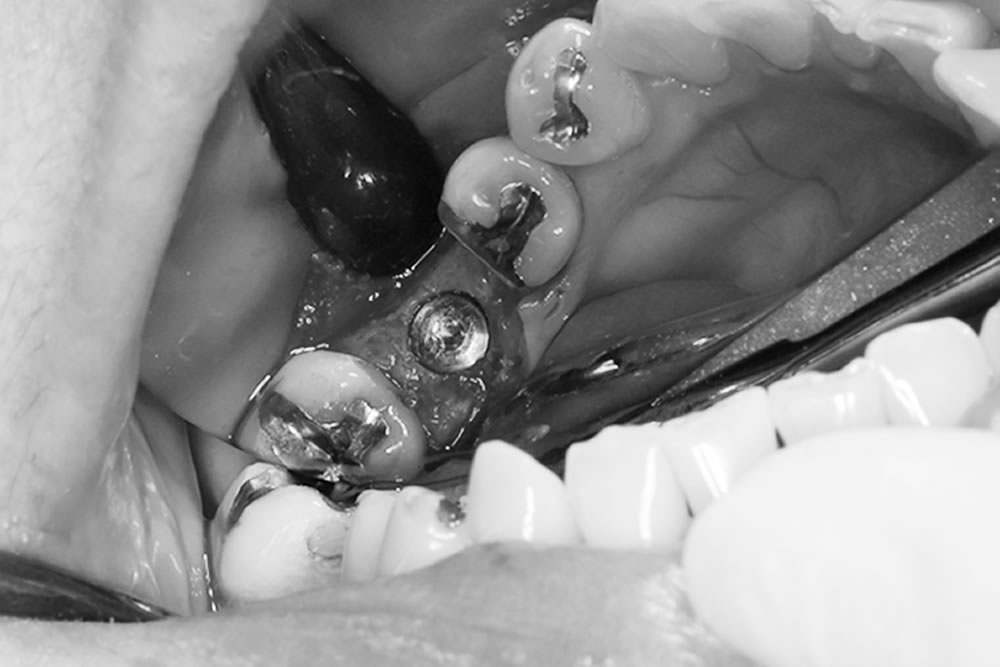

こちらの患者さまは、右下奥歯が腫れて痛みがあり、食べられないとのことで当院に来院されました。

レントゲン上で右下の6番目の根の先端に大きい影が見られます。また左下も噛むと痛みがあるとのことでした。小さい根尖病巣が確認できますが、かなり大きい土台が入っていて再治療が困難な状態なため、患者さまと相談し、右下、左下の大臼歯を抜歯してインプラントで治療する計画を立てました。